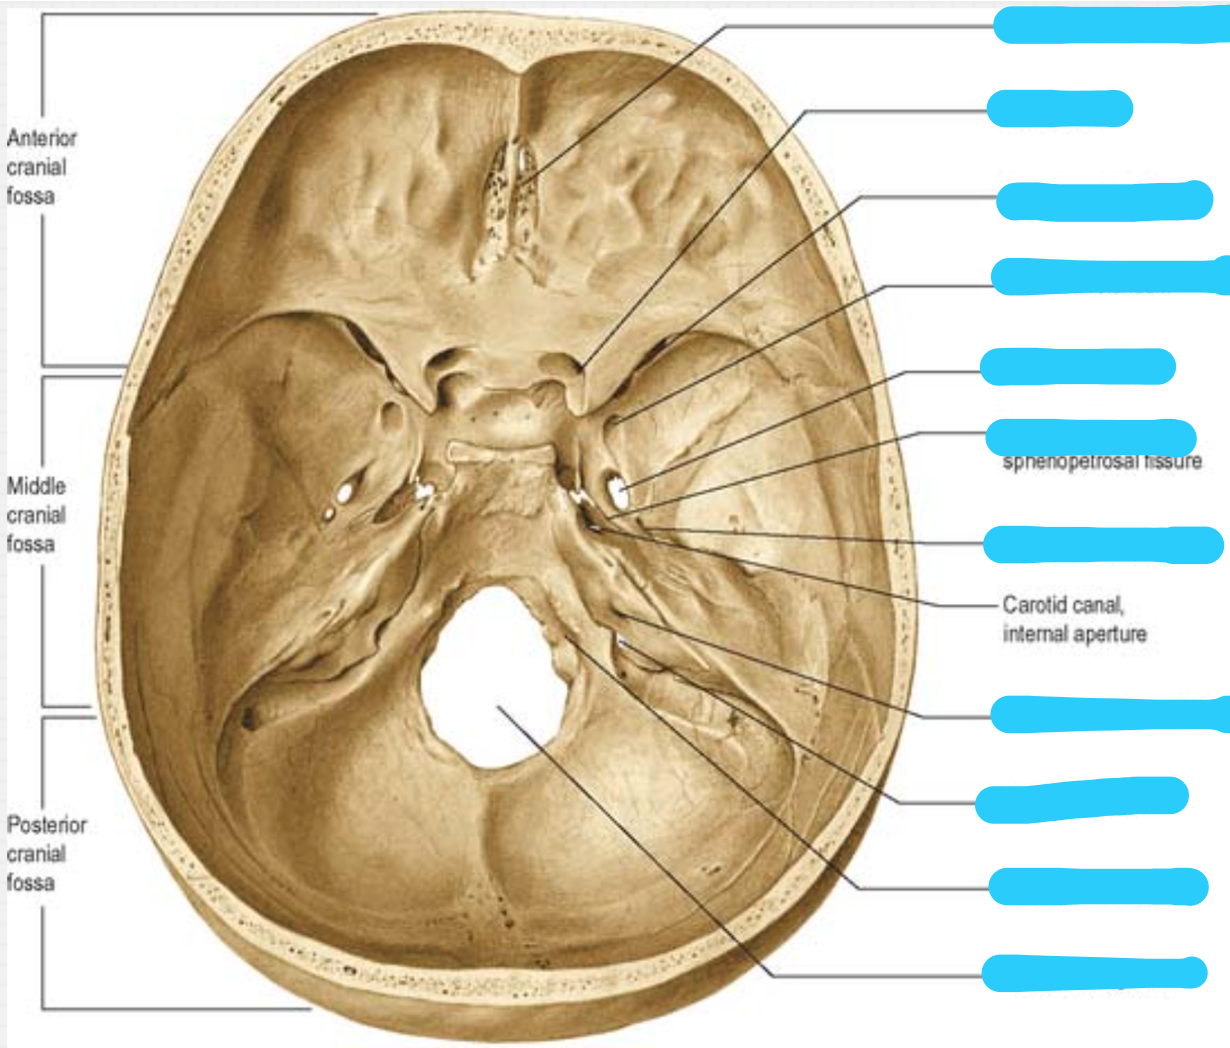

Label the foramen of the skull

Where does the olfactory nerve exit the skull

The cribriform plate of the ethmoid bone

Where does the optic nerve exit the skull

Optic canal

What nerves exit the superior orbital fissure

Occulomotor

trochlear

opthalmic